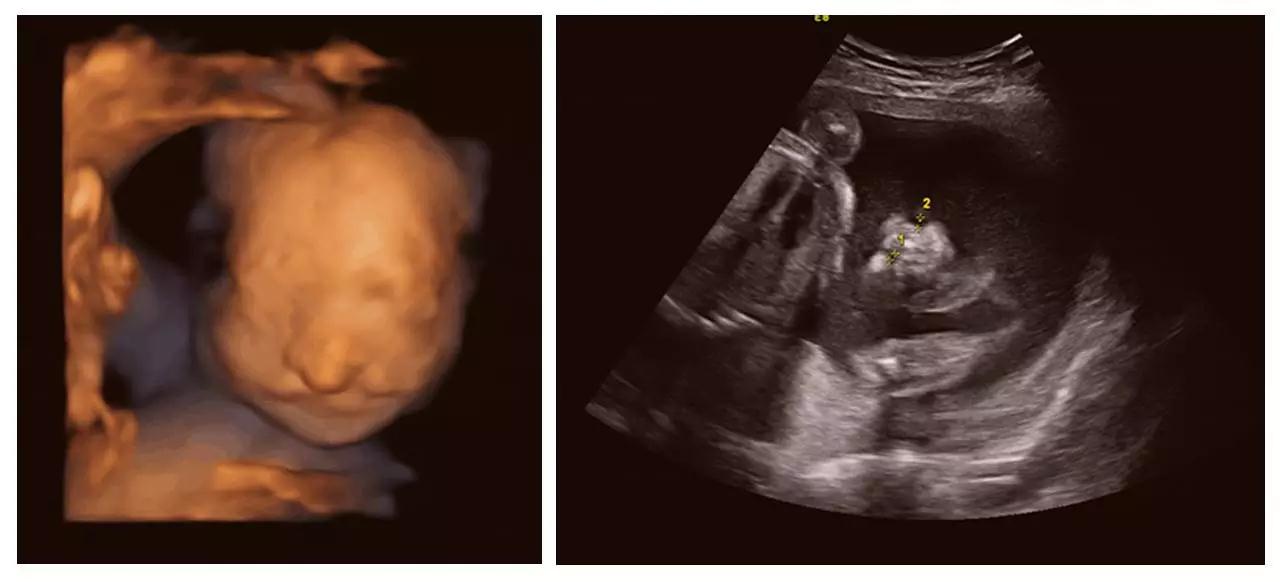

(单侧唇裂)

(双侧唇裂)